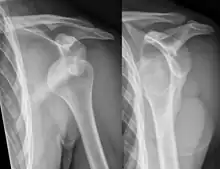

| Anterior dislocation of the left shoulder. | |

In over 95% of shoulder dislocations, the humerus is displaced anteriorly.[8] In most of those, the head of the humerus comes to rest under the coracoid process, referred to as sub-coracoid dislocation. Sub-glenoid, subclavicular, and, very rarely, intrathoracic or retroperitoneal dislocations may also occur.[9]

Anterior dislocations are usually caused by a direct blow to, or fall on, an outstretched arm. The person typically holds his/her arm externally rotated and slightly abducted.[10]

- An anterior dislocation of the shoulder

Anterior dislocation of the right shoulder. AP X ray

Anterior dislocation of the right shoulder. Y view X ray.